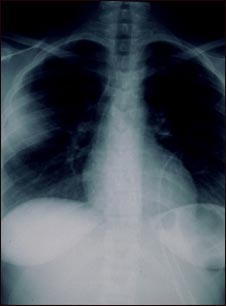

Aspergilosis - radiografía de tórax

La aspergilosis es una infección micótica en la cual un hongo invade y destruye el tejido. Este tipo de infección normalmente se presenta en individuos inmunocomprometidos. En este caso, la radiografía de tórax muestra que el hongo ha invadido el tejido pulmonar. En una radiografía, los pulmones generalmente se ven como áreas oscuras y la opacidad en el lado izquierdo de esta radiografía se debe a la presencia del hongo.